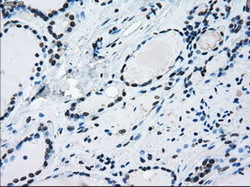

- Immunohistochemical staining of paraffin-embedded Kidney tissue using anti-ERCC1 mouse monoclonal antibody. (Dilution 1:50).

- Submitted by

- LSBio (provider)

- Enhanced method

- Genetic validation

- Main image

- Experimental details